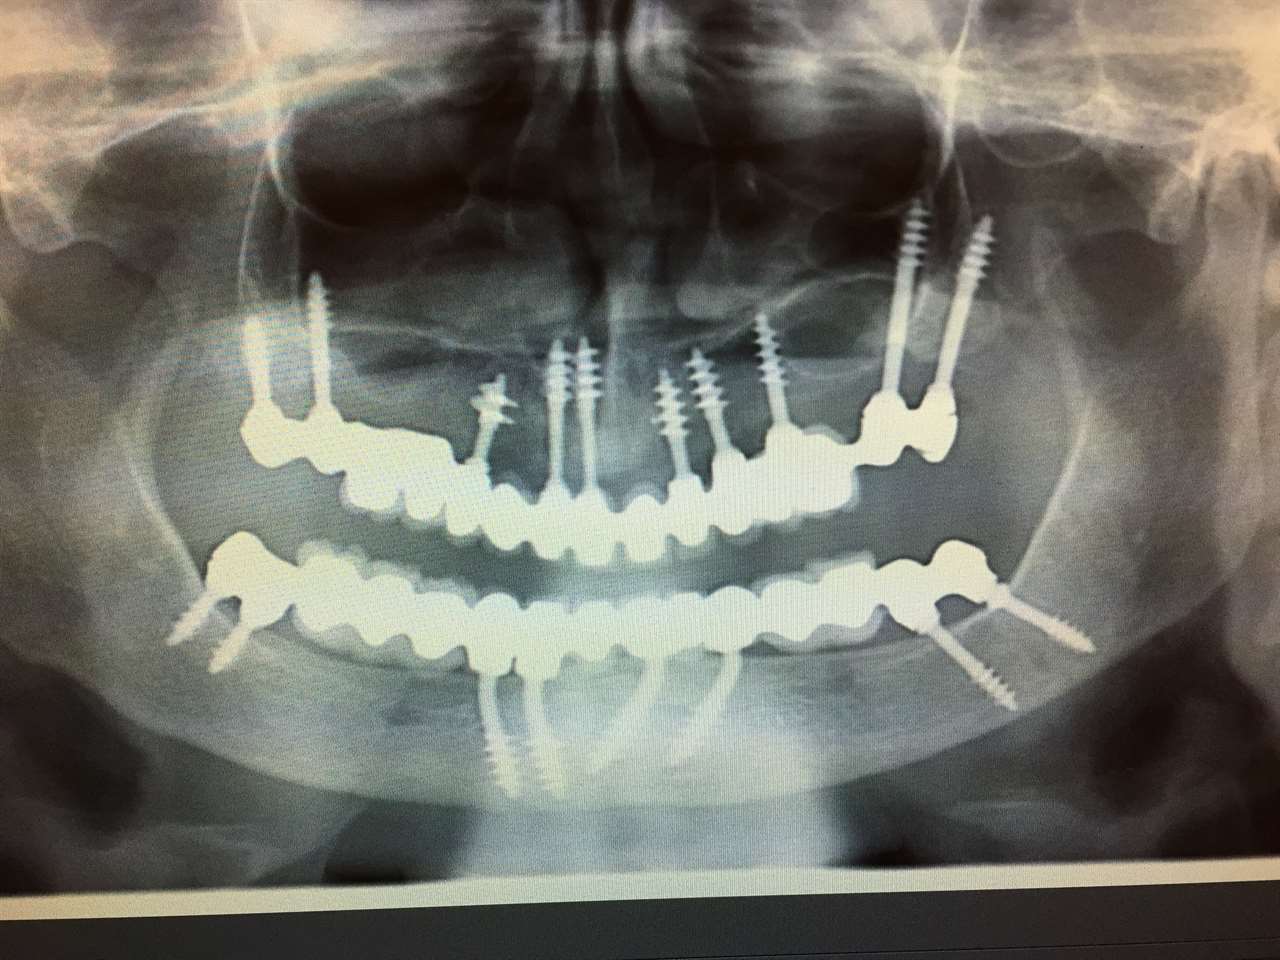

Teljes alsó,felső állcsont helyreállítása azonnal

terhelhető implantátumokkal és porcelán hidakkal.